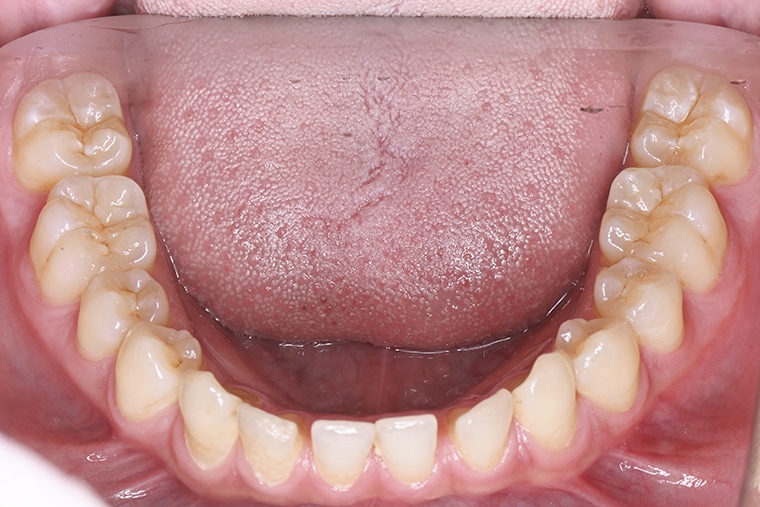

Case Study18歳男性すきっ歯のマウスピース矯正-矯正期間6ヶ月(2024年8月開始)